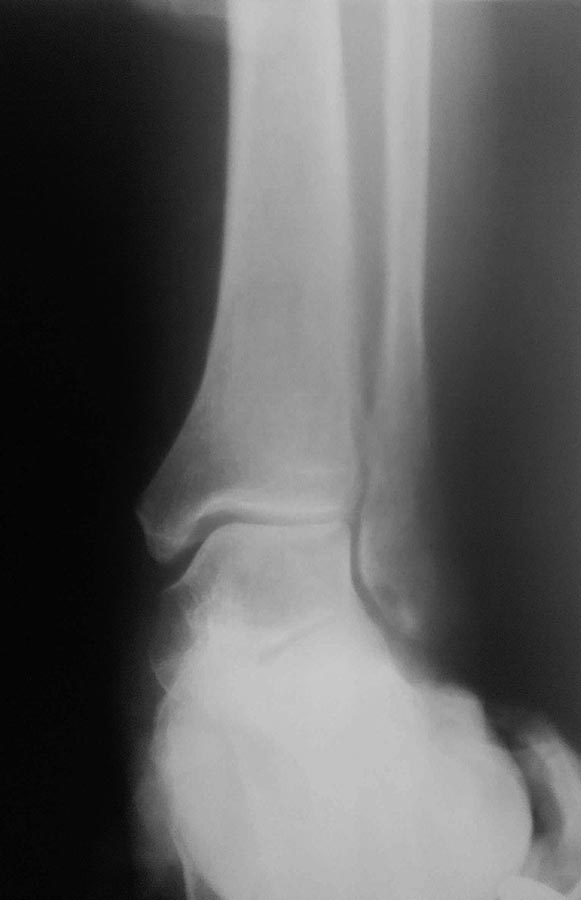

с наружной ротацией и пронацией стопы.